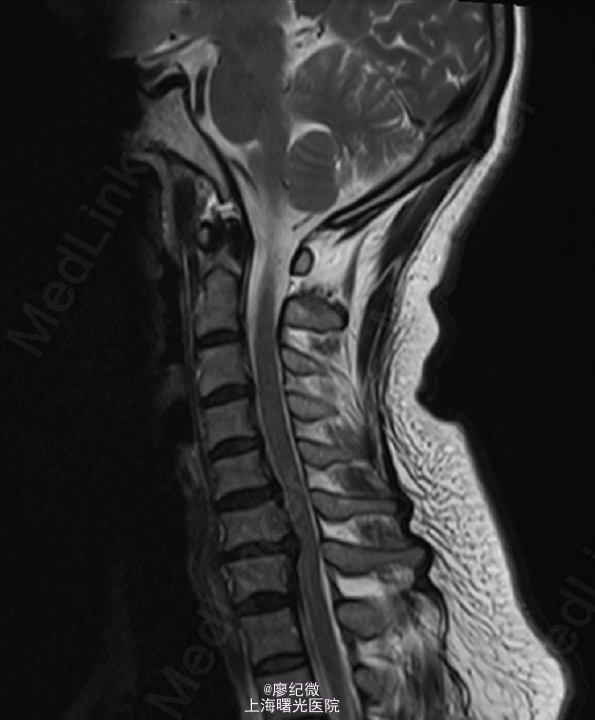

患者,女,48岁,因“左肩背部疼痛伴左食指、中指麻木1月半”入院。 患者1月半前无明显诱因下出现左肩背部疼痛伴左食指、中指麻木,疼痛向左上肢放射。1个半月来上述症状反复存在.

脊柱生理曲度存在,颈项部无明显压痛,颈椎活动无明显受限,全身深浅感觉均存在,左肱三头肌肌力5-级,左食指、中指感觉减退,余无殊.霍夫曼征阴性,膝腱反射无亢进,双侧直腿抬高实验阴性,双侧巴氏征阴性。 当地医院MR:颈6/7椎间盘脱出伴相应椎管狭窄.